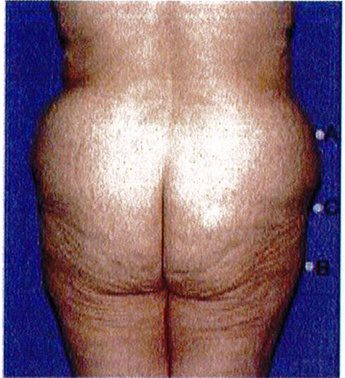

Khung vuông là phổ biến nhất, gặp ở khoảng 40% số bệnh nhân. Vị trí A và B tương tự nhau, đặc trưng cho phần mông hình vuông để khi các điểm này nối với nhau sẽ được một hình vuông (Hình 7 và 8). Điểm C có thể có các mức độ lõm (thiếu mô mỡ) khác nhau. Đây là dạng khung dễ chỉnh hình nhất trong cả 4 kiểu khung vì bất kỳ sự thay đối nào ở 1 trong 3 điểm A,B,C đều có thể biến khung này thành dạng khung khác.

Short Square Buttock – Round implant is best

Short gluteus: height and width is the same (1:1 ratio)

Tall Square Buttock – Best to use an anatomic implant

Tall gluteus: the muscle is taller than it is wide (2:1 ratio)

ình. 8. Hình minh họa khung vuông, cao. Cơ mông lớn có tỉ lệ cao/rộng = ..

Dạng còn lại là dạng trung gian, nằm giữa dạng khung cao và khung thấp vừa mới đề cập ở trên. Cơ mông lớn có chiều cao/rộng = 1:1 hoặc 2:1. Mông dạng vuông thường được cải thiện tương đối nhiều khi hút mỡ điểm A và B. Điểm C có thể cần ghép mỡ, tùy thuộc vào mức độ lõm tại điểm này (Hình 9).

Hình dạng này độc đáo ở chỗ chúng có thể cao, trung bình hoặc ngắn (Hình 7 và 8). Để hiểu rõ khái niệm này, cần phải nhớ rằng khung bao gồm da, mỡ và xương. Khung xương chỉ hữu ích để xác định đây là khung cao, trung bình hay ngắn. Giới hạn trên của khung xương là đường viền trên của mào chậu. Nên tùy thuộc độ cao của chúng mà cơ mông lớn sẽ bám vào khung xương tại các vị trí khác nhau. Cụ thể, biến thể đầu tiên gắn đường viền trên cơ mông lớn dọc Theo đường viền trên của toàn bộ mào chậu, chúng để lại rất ít khoảng trống giữa bờ trên của cơ và mào chậu. Loại này hình thành khung chậu ngắn, tỉ lệ cao/rộng của khối cơ là 1:1. Dạng biến thể thứ hai, cơ bám thấp hơn trên khung chậu, sao cho mép trên của cơ cách mào chậu khoảng ½ chiều dài cơ. Loại này được gọi là khung chậu cao, cơ thường có tỉ lệ cao/rộng là 2:1 (Hình 8)

Hình. 9. Minh họa khung vuông, cao trước (trái) và sau (phải) phầu thuật chỉnh hình mông.